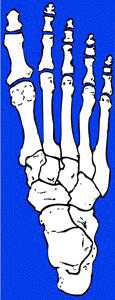

normal foot hallux valgus

NlFoot: HValgus:

normal foot in which the normal intermetatarsal angle measures about 5 - 10 degrees foot with metatarsus primus varus, in which the intermetatarsal angle measures about 20 degrees